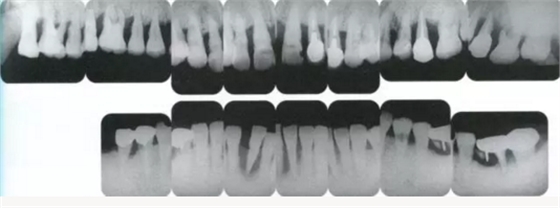

▲圖15-1,2

在正畸??漆t(yī)生處接受了正畸治療,雖然上頜正畸治療已經(jīng)完成,但由于磨牙區(qū)的邊緣嵴不整齊而導致牙體之間存在空隙。要想在這個狀態(tài)下護理牙周組織以及咬合狀況是非常困難的。由此可見,在治療時,正畸專科醫(yī)生與全科口腔醫(yī)生保持目標一致是非常重要的。